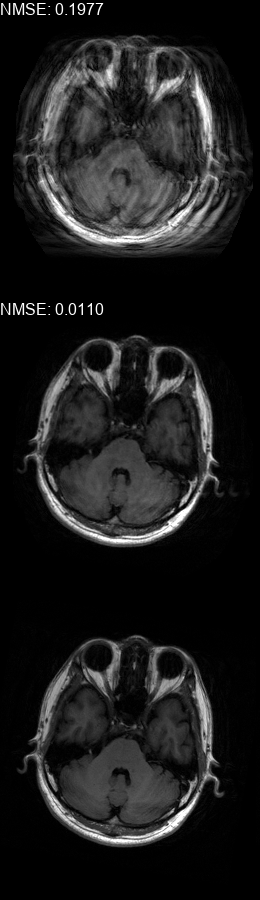

Results  Experimental results using the two presented datasets, for the fully-sampled and under-sampled k𝑘k-space scan orders, are shown in Table 1. The table presents the Normalized Mean Square Error (NMSE) obtained for each of the scan orders. For the Transaxial dataset, we only show the results for the challenging task where the DP contains only up to 707070 columns of k𝑘k-space data. All methods are able to reduce the NMSE of the corrupted scans, however the methods that incorporate the DC layer achieve a much better result. These results match our subjective visual impression of the motion-corrected images, as may be seen in Fig. 3 for simulated motion in a fully-sampled k𝑘k-space data, and Fig. 4 for an under-sampled k𝑘k-space data.

Figure 3: Motion corrected images from the Diverse dataset calculated using the 𝒮260subscript𝒮260\mathcal{FS}_{260} scan order presented in Fig. 1b. The bottom row shows the motion-free image. The top row shows the motion-corrupted images. The middle row shows the corrected images calculated using our method. (a) contains a motion at t1=87subscript𝑡187t_{1}=87, (b) contains two motions at t1=46subscript𝑡146t_{1}\!=\!46, t2=170subscript𝑡2170t_{2}\!=\!170, (c) contains three motions at t1=72subscript𝑡172t_{1}\!=\!72, t2=227subscript𝑡2227t_{2}\!=\!227, t3=248subscript𝑡3248t_{3}\!=\!248, (d) contains two motions at t1=112subscript𝑡1112t_{1}\!=\!112, t2=216subscript𝑡2216t_{2}\!=\!216, (e) contains a motion at t1=66subscript𝑡166t_{1}\!=\!66, (f) contains three motions at t1=65subscript𝑡165t_{1}=65, t2=135subscript𝑡2135t_{2}\!=\!135, t3=159subscript𝑡3159t_{3}\!=\!159.